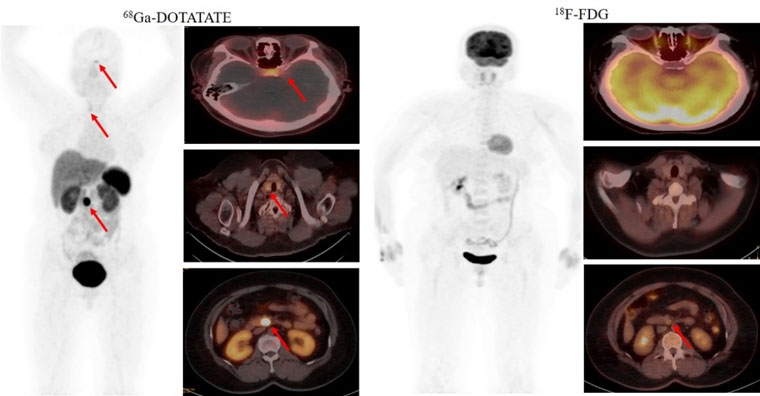

首个病例患者为一名49岁的女性,间断低血糖超过1年,甲状旁腺激素检查异常升高。脑MRI提示为脑垂体微腺瘤,上腹部MRI检查未发现明显异常。但临床怀疑胰腺存在病变,经新探针68Ga-DOTATATE PET/CT检查,发现了胰腺病灶,综合诊断多发性内分泌瘤病I型(MEN1型)。经胰腺穿刺病理证实为神经内分泌肿瘤G2。68Ga-DOTATATE及18F-FDG PET/CT双核素的检查结果为患者临床精准诊疗提供了胰腺病灶的影像学证据。

2021年5月,我院核医学科率先获得河北省最高级别的IV类放射性药品使用证书。在学科带头人赵新明教授的带领下,科室成员汲取全国优秀核医学科经验,成功开展了多种新型分子探针PET/CT临床显像工作。这些新型分子影像探针包括68Ga-DOTATATE(68Ga-生长抑素受体激动剂,针对神经内分泌肿瘤)、68Ga-JR11(68Ga-生长抑素受体拮抗剂,针对神经内分泌肿瘤)、68Ga-FAPI(68Ga-成纤维细胞活化蛋白抑制剂,针对肿瘤微环境中肿瘤相关成纤维细胞,用于各种肿瘤显像)和68Ga-PSMA(68Ga-前列腺特异性膜抗原,针对前列腺癌等多种恶性肿瘤)等,新型PET分子探针(显像剂)的应用对相关肿瘤诊断、分期和疗效评价产生了质的飞跃。